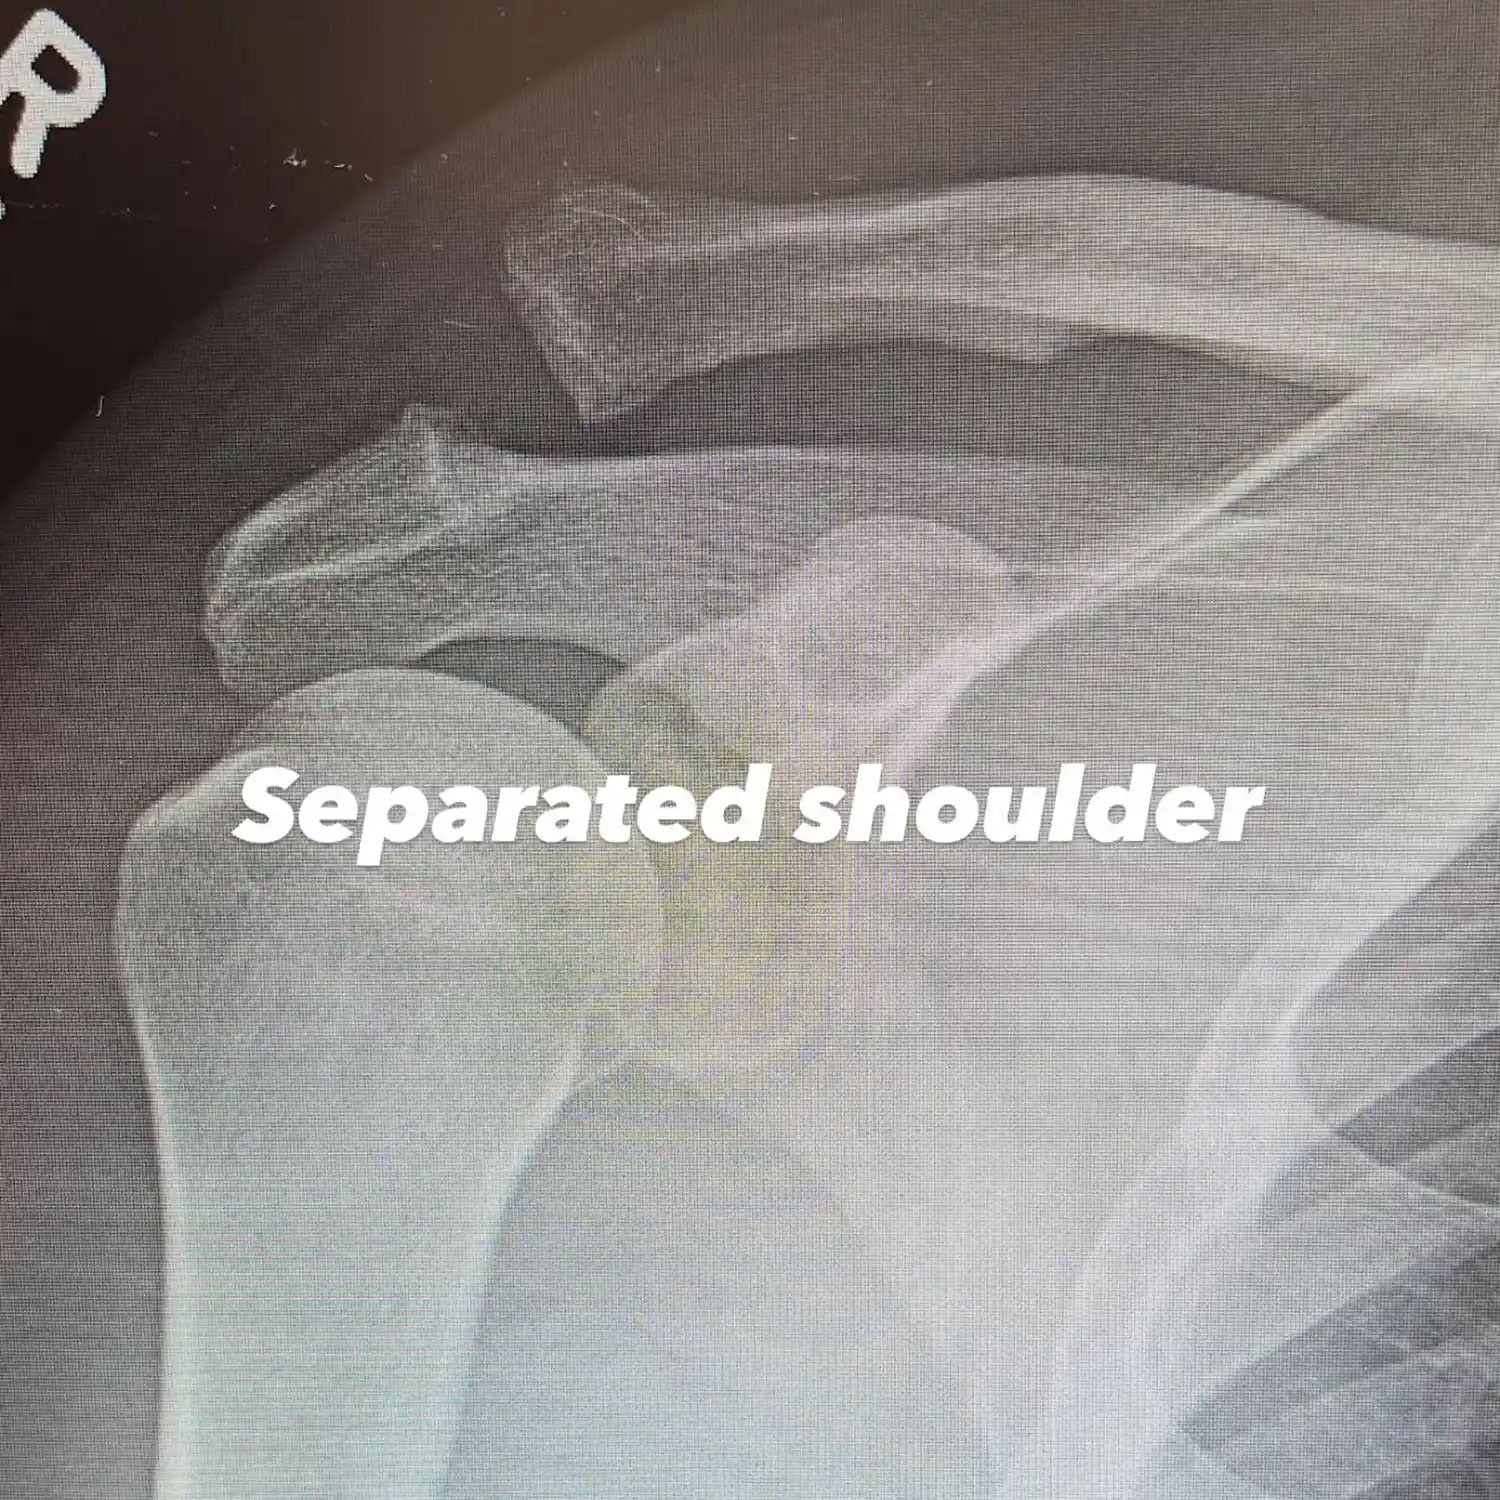

In addition, he shares a series of X-Ray photos, one of which shows a large screw holding the bones of his upper arm.

“Separated shoulder,” he pens, in another picture on Instagram Stories, he writes, “Screwed shoulder. Yay."